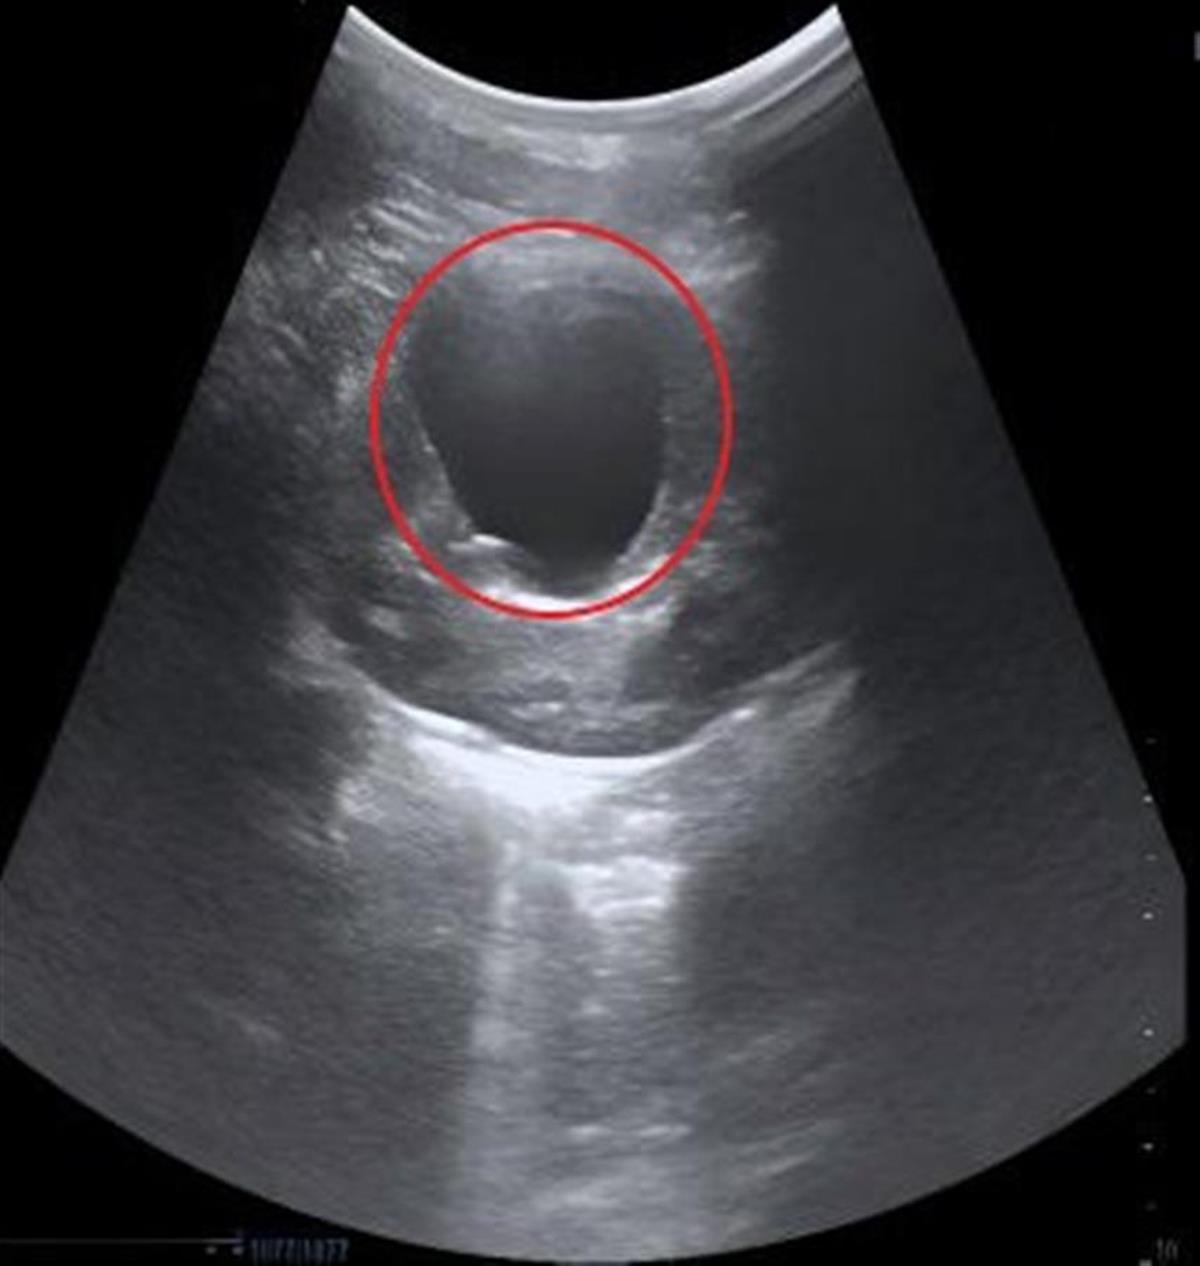

“去年一整年,这个囊肿都挺‘安分’的,可半个月前复查时,囊肿却长到了乒乓球大小。”浩浩妈妈回忆,当时的超声及CT检查结果提示,孩子的囊肿达到BosniakII级,大小约45×40毫米,因为担心囊肿继续增大影响健康,一家人赶紧来到武汉儿童医院泌尿外科就诊。

术前超声检查结果(红圈内为囊肿)